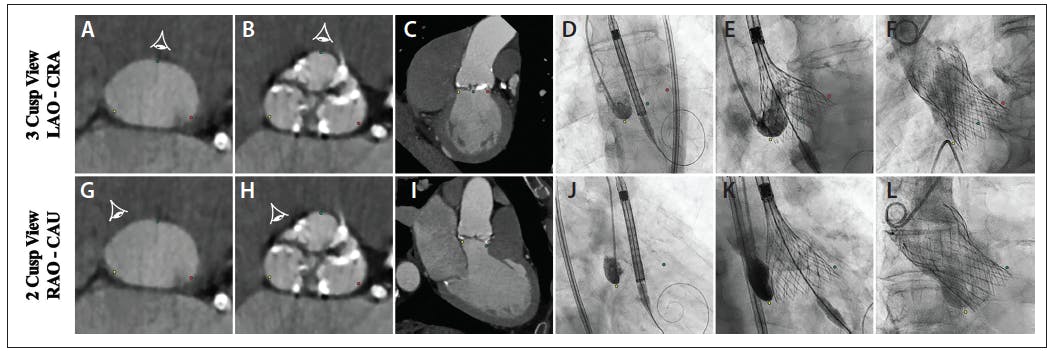

More recently, Gada and colleagues recognized that in the RAO-caudal implant view, the RCC and the left coronary cusp (LCC) are superimposed on MSCT, leaving the NCC isolated. This two-cusp view, or cusp overlap view, is distinct from the traditional three-cusp view that is found usually in an LAO-cranial projection (Figure 3). This important observation affords TAVR operators the ability to efficiently and simply identify a suitable RAO-caudal implantation view without the need for dedicated MSCT software. The technique is performed by overlapping the RCC and LCC (cusp overlap view) and isolating the NCC while riding along the annular S-curve on the pre-TAVR MSCT.18 Similar to the double S-curve view, the cusp overlap view occurs in the RAO-caudal projection in the majority of cases.

Figure 3. Cusp overlap technique. Traditional three-cusp view where all three cusps are visible, generally corresponding to an LAO-CRA view (A-C). In this view, the NCC (yellow dot) is on the left side, the RCC (green dot) is in the middle, and the LCC (red dot) is on the right side. THV positioning, deployment, and final assessment under a 3-cusp view (D-F). New 2-cusp view where the LCC and the RCC are overlapped and the NCC is isolated, generally corresponding to an RAO-CAU view (G-I). In this view, the NCC (yellow dot) remains on the left side while the RCC (green dot) and the LCC (red dot) are overlapped on the right side. THV positioning, deployment, and final assessment under a 2-cusp view (J-L). CAU, caudal; CRA, cranial; LAO, left anterior oblique; LCC, left coronary cusp; NCC, non-coronary cusp; RAO, right anterior oblique; RCC, right coronary cusp; THV, transcatheter heart valve.